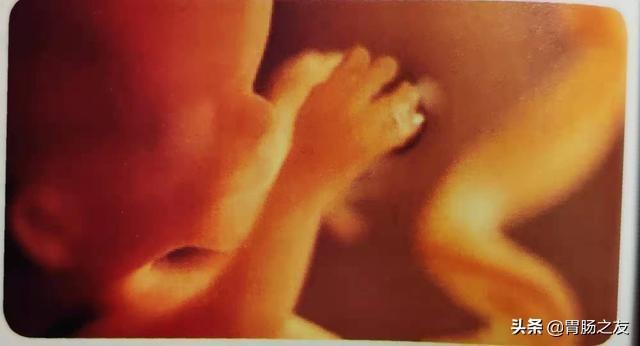

此三维超声图像显示一个13周的胎儿正在用手触碰脸颊。此时,胎儿所有的关节已经形成,可行一系列的运动。